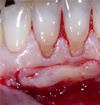

Photos extraites du diaporama :